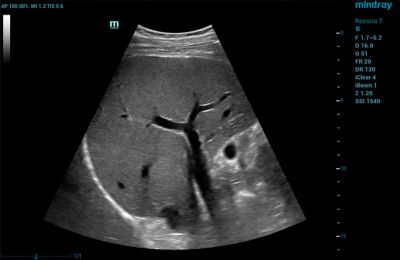

1. High-Resolution Images

Image quality and image-enhancing feature sets are typically top of mind when looking for a new ultrasound machine. The quality of the image directly impacts patient care, so it is important that you select a system that provides the quality you need to arrive at the appropriate diagnoses.

When evaluating a machine, pay careful attention to image resolution. For instance, ensure the machine offers excellent contrast resolution — its ability to distinguish between tissues with different levels of brightness. A high-quality ultrasound machine will show the subtle differences between tissues to enable a precise diagnosis.

Also, consider software features that enhance image clarity and reduce unwanted artifacts — images that don't represent real anatomical structures. This includes image processing algorithms like speckle reduction and spatial compounding, which reduce noise and improve image quality.

If you're purchasing ultrasound machines for a multi-specialty facility, it's important to look for systems that offer a wide transducer breadth. For example, the Resona I9 Ultrasound System features multiple active transducer ports to support a comprehensive transducer family, including convex and linear transducers. This allows the technology to be used across departments and reduces the need to purchase multiple specialized machines.